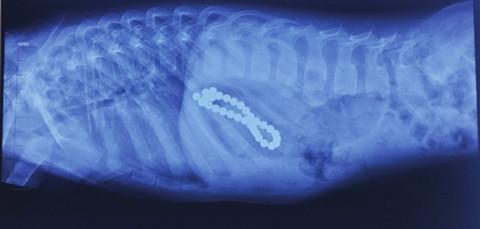

我們一家人趕緊帶着這貨誤了寵物醫院,醫生一檢查,果然在這伙肚子里!但是由於這貨精神狀態還特別好,而且珍珠項鏈很光滑,基本沒有可以傷到它腸胃的地方,所以醫生建議先讓它回家觀察,能自己排出來最好,實在排不出來在做手術!沒辦法,把這貨帶回家后,都不敢帶它出去遛彎,生怕這貨把珍珠項鏈拉到外面我們沒發現。